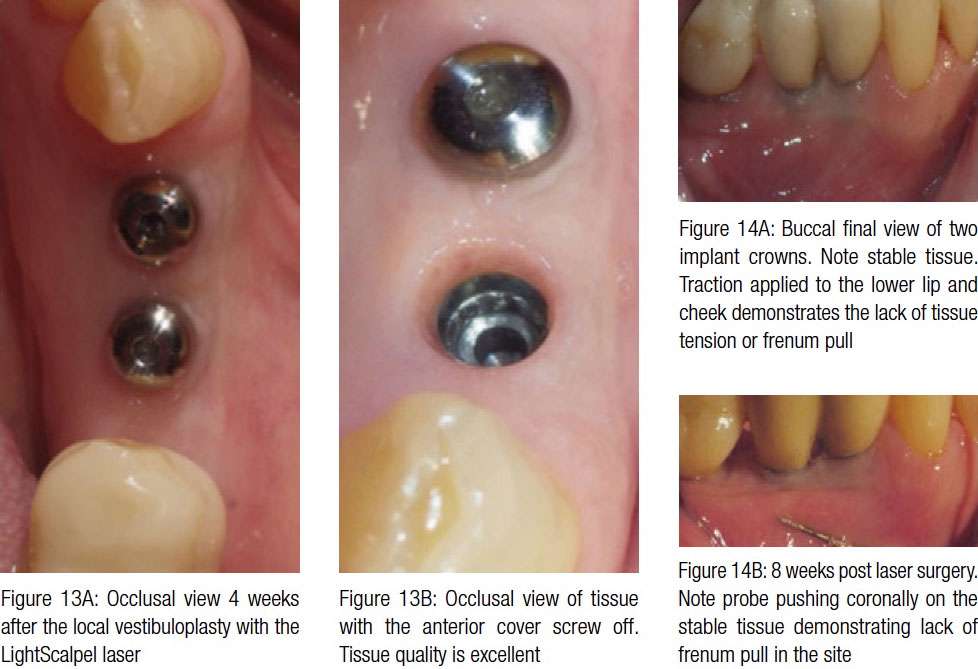

Follow-up examination: Two weeks after the procedure, the patient returned for a check-up. Healing progressed well. No signs of swelling or inflammation were noted. The patient did not express any complaints during the postoperative period. The 4-week follow-up visit showed beautifully healed tissue with no scarring (Figures 13A and 13B). The recovery was uneventful. Figures 14A and 14B present the buccal final view of two implant crowns in place and stable soft tissue. Traction applied coronally with a perio probe demonstrates the lack of frenum pull or mucosal tension at the site (compare with pre-vestibuloplasty view in Figure 11A).